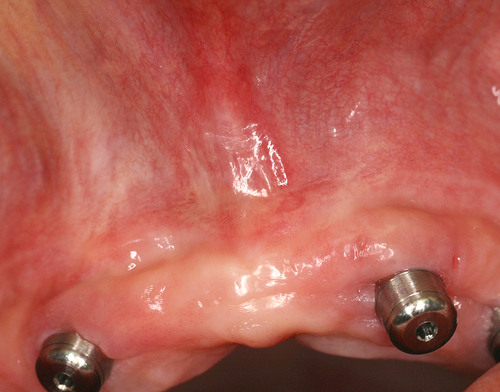

Le résultat obtenu en moins de 3 semaines montre la parfaite réaction des tissus gingivaux à cet acte chirurgical. (fig.25)

Fig. 25